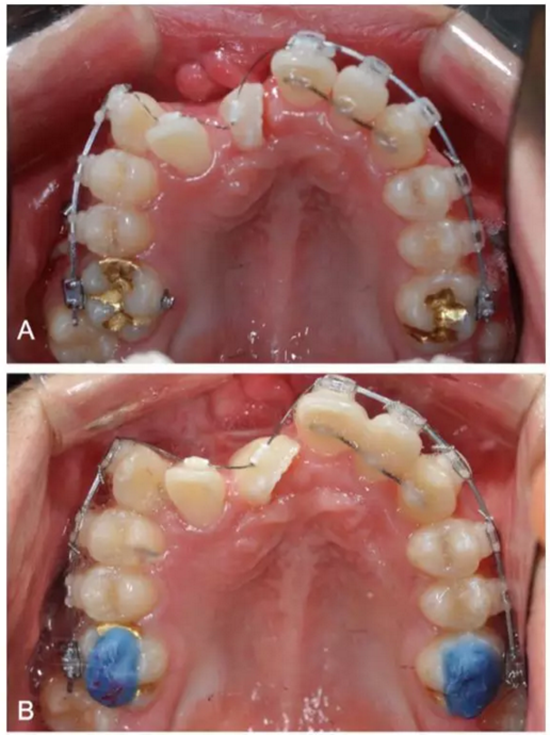

上頜后牙、下頜全牙弓粘接0.22-inch新型陶瓷自鎖托槽。在第二前磨牙及第一磨牙間使用C型管(延伸臂+固定螺絲),以遠(yuǎn)中移動(dòng)上頜后牙。上頜前牙矯正、導(dǎo)萌所需間隙足夠后,使用0.016-inch鎳鈦絲糾正左側(cè)切牙旋轉(zhuǎn),并繼續(xù)使用0.016*0.025-inch鎳鈦方絲、0.016*0.022-inch不銹鋼絲進(jìn)行排齊整平。

第二階段:

弓絲換至0.019*0.025-inch不銹鋼絲時(shí),開(kāi)始進(jìn)行外科手術(shù)暴露阻生牙。由于易位情況嚴(yán)重,三維向阻擋嚴(yán)重,因此需要行兩期手術(shù)。

一期手術(shù)主要是牽引側(cè)切牙和尖牙:于上頜前牙區(qū)唇側(cè)作切口,翻全厚瓣;腭側(cè)面較??;在尖牙唇側(cè)、側(cè)切牙腭側(cè)粘扣掛結(jié)扎絲牽引,通過(guò)一輔助鈦板及樹(shù)脂等連接至弓絲上;采用閉合式導(dǎo)萌技術(shù),將皮瓣復(fù)位縫合,僅結(jié)扎絲穿過(guò)粘膜;2周內(nèi)軟組織得以愈合,牽引開(kāi)始。先通過(guò)正畸力,近中移動(dòng)側(cè)切牙,遠(yuǎn)中移動(dòng)尖牙。10個(gè)月后,阻生牙牙冠萌出,側(cè)切牙、尖牙的易位得以矯正。